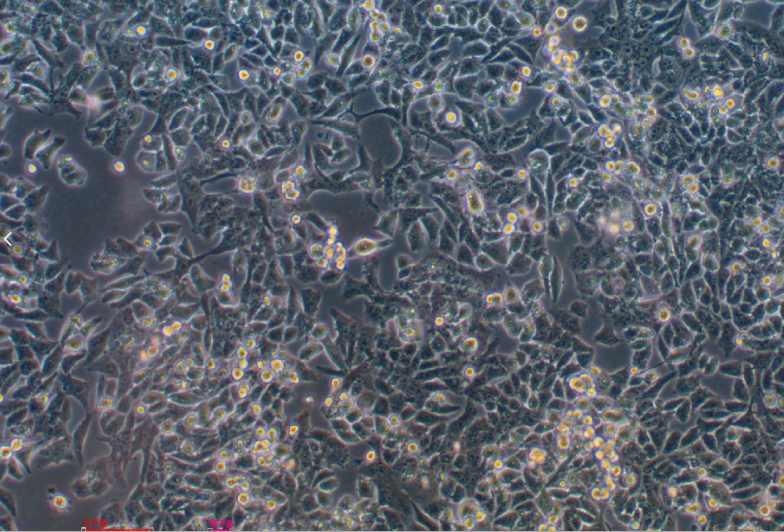

細胞名稱 人胰腺癌吉西他濱耐藥細胞MIA-PACA-2/GEM

生長特性 貼壁生長

細胞形態(tài) 上皮細胞樣